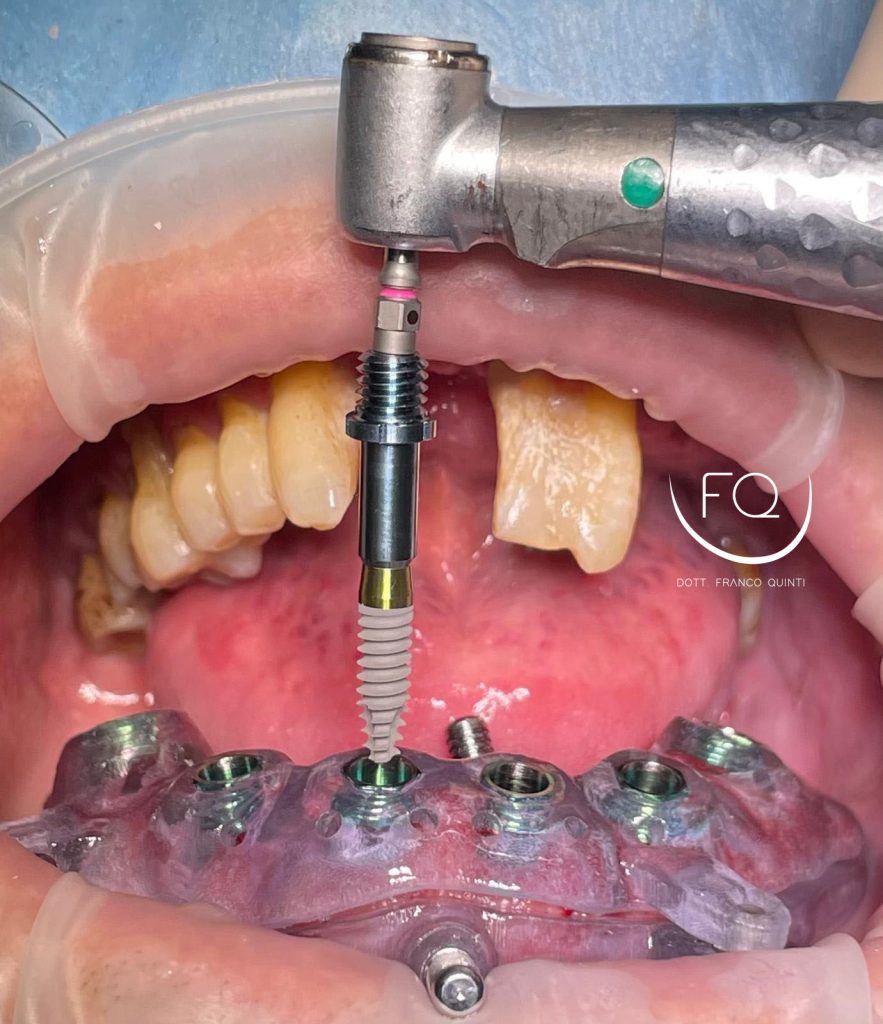

Questa settimana vi presento un caso di chirurgia computer guidata dell’arcata superiore realizzato con dime scomponibili con esecuzione contestuale di un carico immediato.